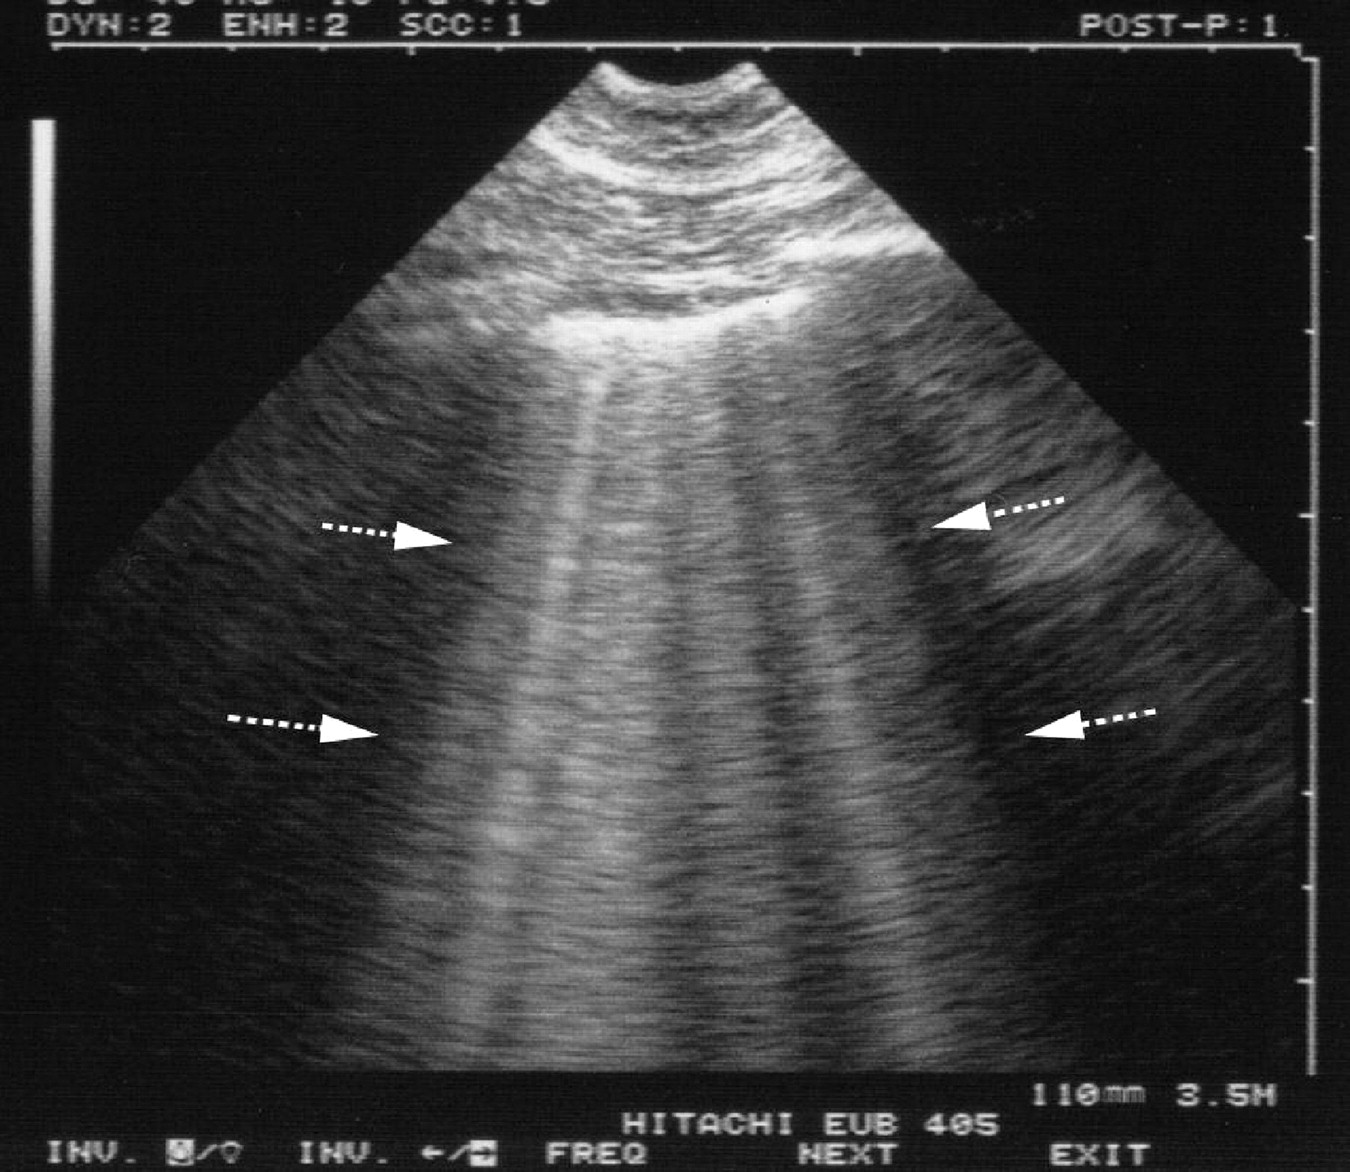

Point of Care Ultrasound1

• B lines seen on lung ultrasound

• The presence of ≥3 B-lines per rib space suggests the presence of interstitial pulmonary fluid

• Cardiogenic pulmonary oedema generates a pattern of diffuse B-lines throughout the chest with thin pleural interfaces

• Non-cardiogenic pulmonary oedema shows a patchy distribution of B-lines anda. thickened pleural interface

• Consider POCUS in patients with undifferentiated respiratory distress

• POCUS may identify a ruptured valve causing acute pulmonary oedema and escalate the need for cardiothoracic intervention